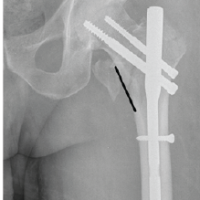

Among the study patients, external fixation was achieved either with the Ilizarov ring fixator or the LRS. A representative case from the Ilizarov group is illustrated in Fig. 1, while two patients treated with the LRS fixator is shown in Fig. 2 and 3.

Figure 2: 38-year-old male patient with compound Grade III B diaphyseal fracture of both bone leg presenting after 3 weeks of injury (a) anteroposterior and lateral views of the affected limb on presentation (b) immediate post-operative radiograph after application of limb reconstruction system (LRS) with corticotomy. (c, d, e) sequential radiographs at 3, 6, and 9 months follow-up, respectively, showing distraction of the fragment and consolidation of the regenerate. (f) Radiograph after removal of the LRS. (g) Wound at presentation. (h) Healthy Granulation of the wound after 1 month. (i) Wound at 3 months follow-up after surgical release of the incarcerated tissue.